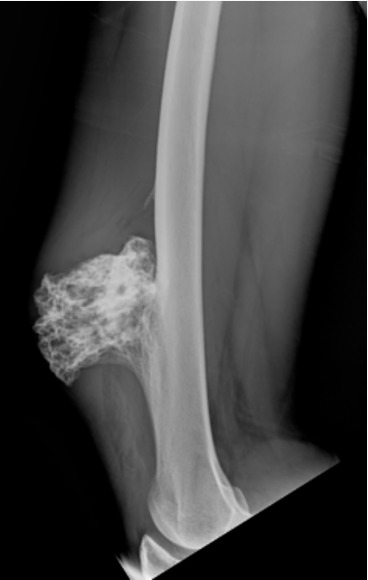

A suspeita de um tumor ósseo é feita através da avaliação minuciosa da queixa do paciente e exame físico. A partir da suspeita é realizada a triagem de exames que envolve Radiografias, Tomografia Computadorizada, Ressonância Magnética e Cintilografia Óssea, além de exames de sangue. Após o estudo dos exames, pode ser recomendada a biópsia do tecido do tumor. A biópsia é um procedimento que auxilia a especificar qual tumor e sua agressividade. Ela pode ser feita por meio de uma incisão ou por agulha.

Condrossarcoma: É um tumor maligno primário que forma cartilagem. Acomete principalmente os adultos, nos ossos da bacia, fêmur e úmero.